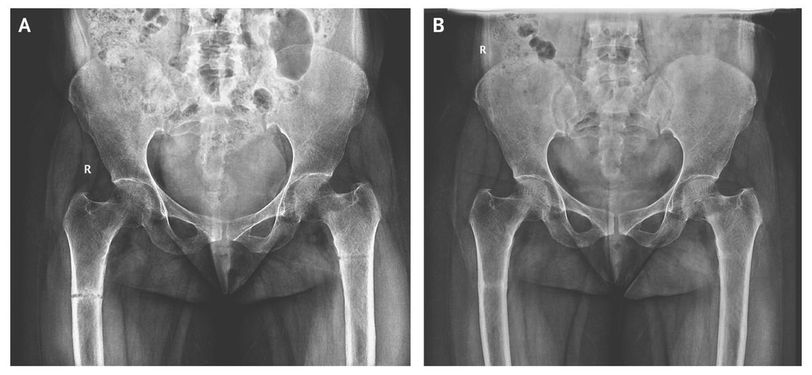

A 45-year-old woman presented with a 3-month history of generalized body pains that were nonresponsive to analgesic agents. Along with low back pain, she had progressive difficulty in getting up from sitting and supine positions and in walking. There was no history of trauma or any medication intake. She is an orthodox Muslim woman who wears a black veil outdoors and is completely covered, with little exposure to the sun, even in her courtyard. On examination, she had a waddling gait with painful movements of both thighs. The serum calcium level was 8.4 mg per deciliter (2.1 mmol per liter) (reference range, 8.0 to 10.4 mg per deciliter [2.0 to 2.6 mmol per liter]), the phosphate level 1.5 mg per deciliter (0.5 mmol per liter) (reference range, 2.5 to 4.5 mg per deciliter [0.8 to 1.5 mmol per liter]), the alkaline phosphatase level 916 U per liter (reference range, 30 to 120), and the 25-hydroxyvitamin D level 9 nmol per liter (reference range, 18 to 100). An anteroposterior radiograph of the pelvis showed an undisplaced transverse fracture of the shaft of both femurs (Panel A). The patient was treated with therapeutic doses of calcium and vitamin D supplements. After 3 weeks, her symptoms had improved substantially, and she walked with minimal pain. Blood tests showed an increase in the phosphate level to 3.0 mg per deciliter (1.0 mmol per liter) and a decrease in the alkaline phosphatase level to 418 U per liter. A follow-up radiograph showed healed fractures (Panel B). Patients with osteomalacia may present with generalized osteopenia. A radiographic study may show cortical stress fractures, often called Looser zones or pseudofractures, which are seen as bilateral, symmetric, radiolucent lines in the bone cortex perpendicular to the long axis. Looser zones contain fibrous tissue and poorly mineralized callus and are often found on the ribs, the femoral neck, the pubic rami, and the axillary margins of the scapulae. Vaishali Tomar, M.D. Vijaya Medical Centre, Visakhapatnam, India Vishnu V. Reddy Munagala, M.D. Vizag Rheumatology and Immunology Centre, Visakhapatnam, India Source: nejm.org